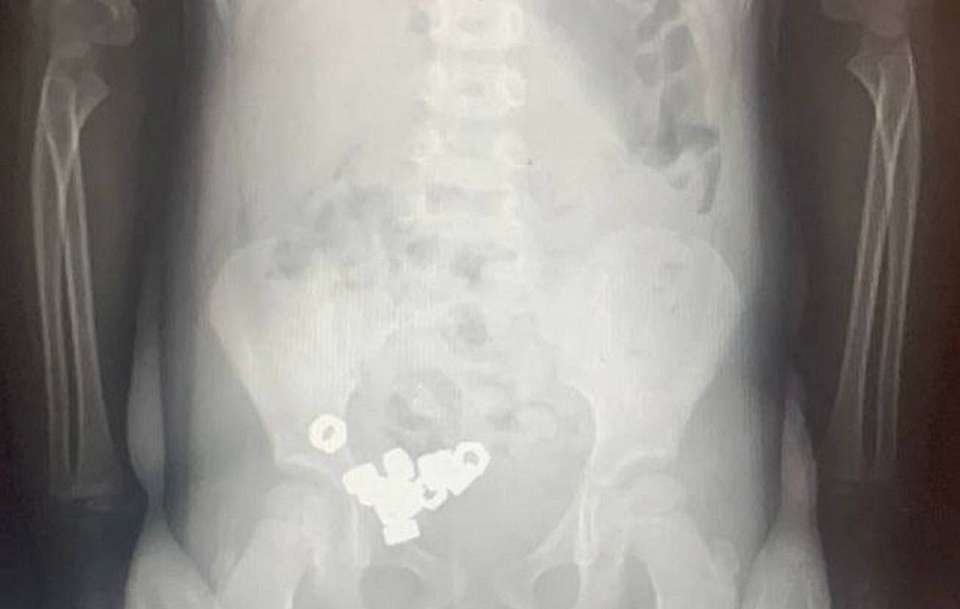

Осмотр не выявил каких-либо специфичных симптомов, однако проведённый рентген органов живота зафиксировал присутствие множества контрастных теней (шестнадцать небольших гаечек) внутри пищеварительного тракта ребёнка, сообщили в региональном Минздраве.